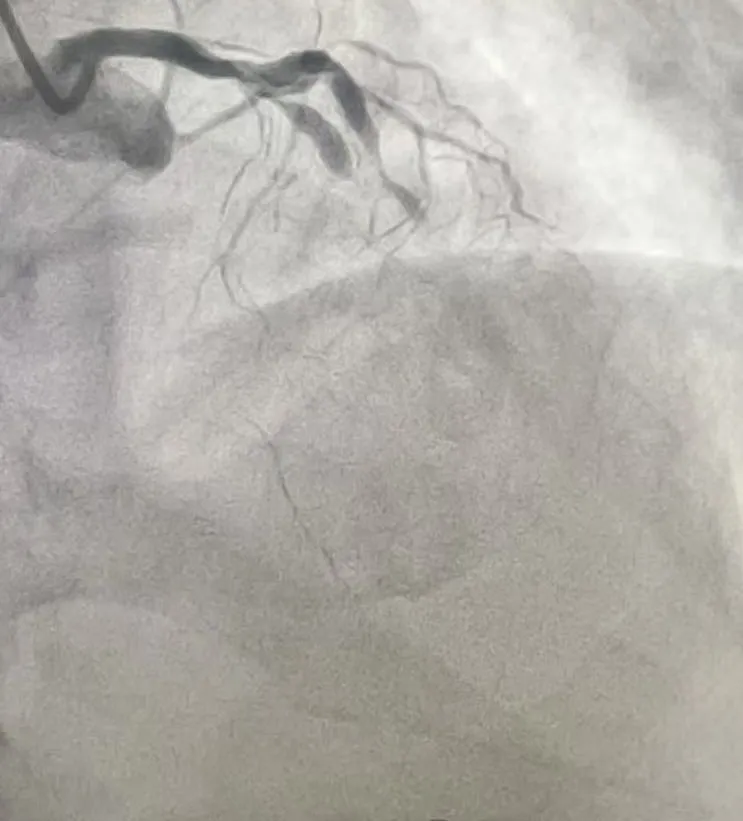

心脏血管造影检查提示,张先生的三支主要血管均存在严重病变。

• 前降支近段完全闭塞,该血管心脏供血的“主干道”之一,负责左心室前壁血液供应,堵塞后极易引发大面积心梗;

• 回旋支中远段完全闭塞,供应心脏侧壁血液,闭塞会加重心肌缺血范围;

• 右冠状动脉中远段弥漫性狭窄,最重处达70%-80%,虽未完全堵死,但狭窄严重,随时可能进展为急性闭塞。

(术前影像)

患者前降支和回旋支同时完全堵塞,相当于心脏的两条重要“高速公路”彻底中断,仅靠右冠残余血流勉强维持,随时可能猝死。